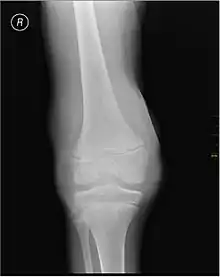

Synovial Fluid analysis is another method to diagnose Hemarthrosis. It involves a small needle being inserted into the joint to draw the fluid.[7] Reddish-colored hue of the sample is an indication of the blood being present. Imaging tests are normally done. The tests also include MRI, Ultrasound and X-ray test, which give better information about the joint inflammation.[8]